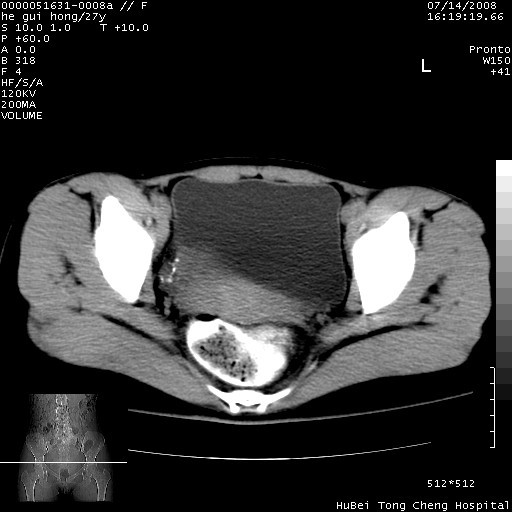

以下是引用杀毒软件在2008-7-20 8:03:00的发言:[br]支持双侧卵巢囊腺瘤可能性大!

以下是引用zjzjr在2008-7-20 13:36:00的发言:[br]双侧附件囊腺瘤可能性大!